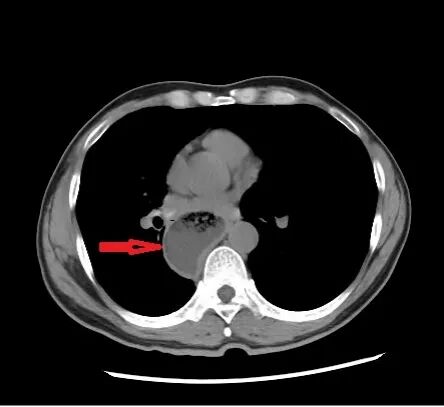

患者收治入院后,医生先后为其完成胃镜、上消化道造影、腹部CT等专科检查。胃镜检查提示,食管下端呈典型“鸟嘴样”改变,胃镜通过困难,食管上段明显扩张;上消化道造影提示,食管下端狭窄呈鸟嘴状,食管整体扩张、蠕动减弱,钡剂通过贲门受阻;腹部CT提示,食管扩张明显,管腔内可见积液积气。

结合症状与影像学检查,患者最终被诊断为贲门失弛缓。针对患者的病情,胃肠外科诊疗团队迅速开展病例讨论,全面评估患者身体状况,制定了个体化微创治疗方案——腹腔镜下贲门肌切开+Dor胃底折叠术,并完善了术前各项准备工作。